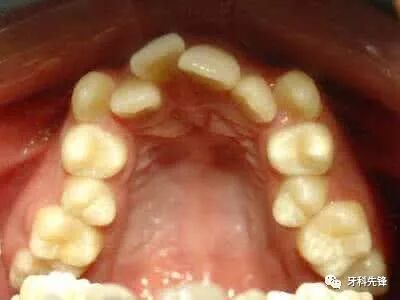

牙齿正畸是医生通过矫治器给牙齿一个外力,从而让牙槽骨发生改建,带动牙齿移动。但很多人的口腔存在着牙骨量不协调的问题,也就是说,牙齿量大于骨骼量,牙齿的周长大于颌骨的周长,导致牙齿拥挤和排列不齐等问题。

所以,如果是这样的情况,就需要通过拔牙来挪出空间让其他牙齿移动,最终排列整齐,进而改善咀嚼功能、让面型更好看。

牙列拥挤者